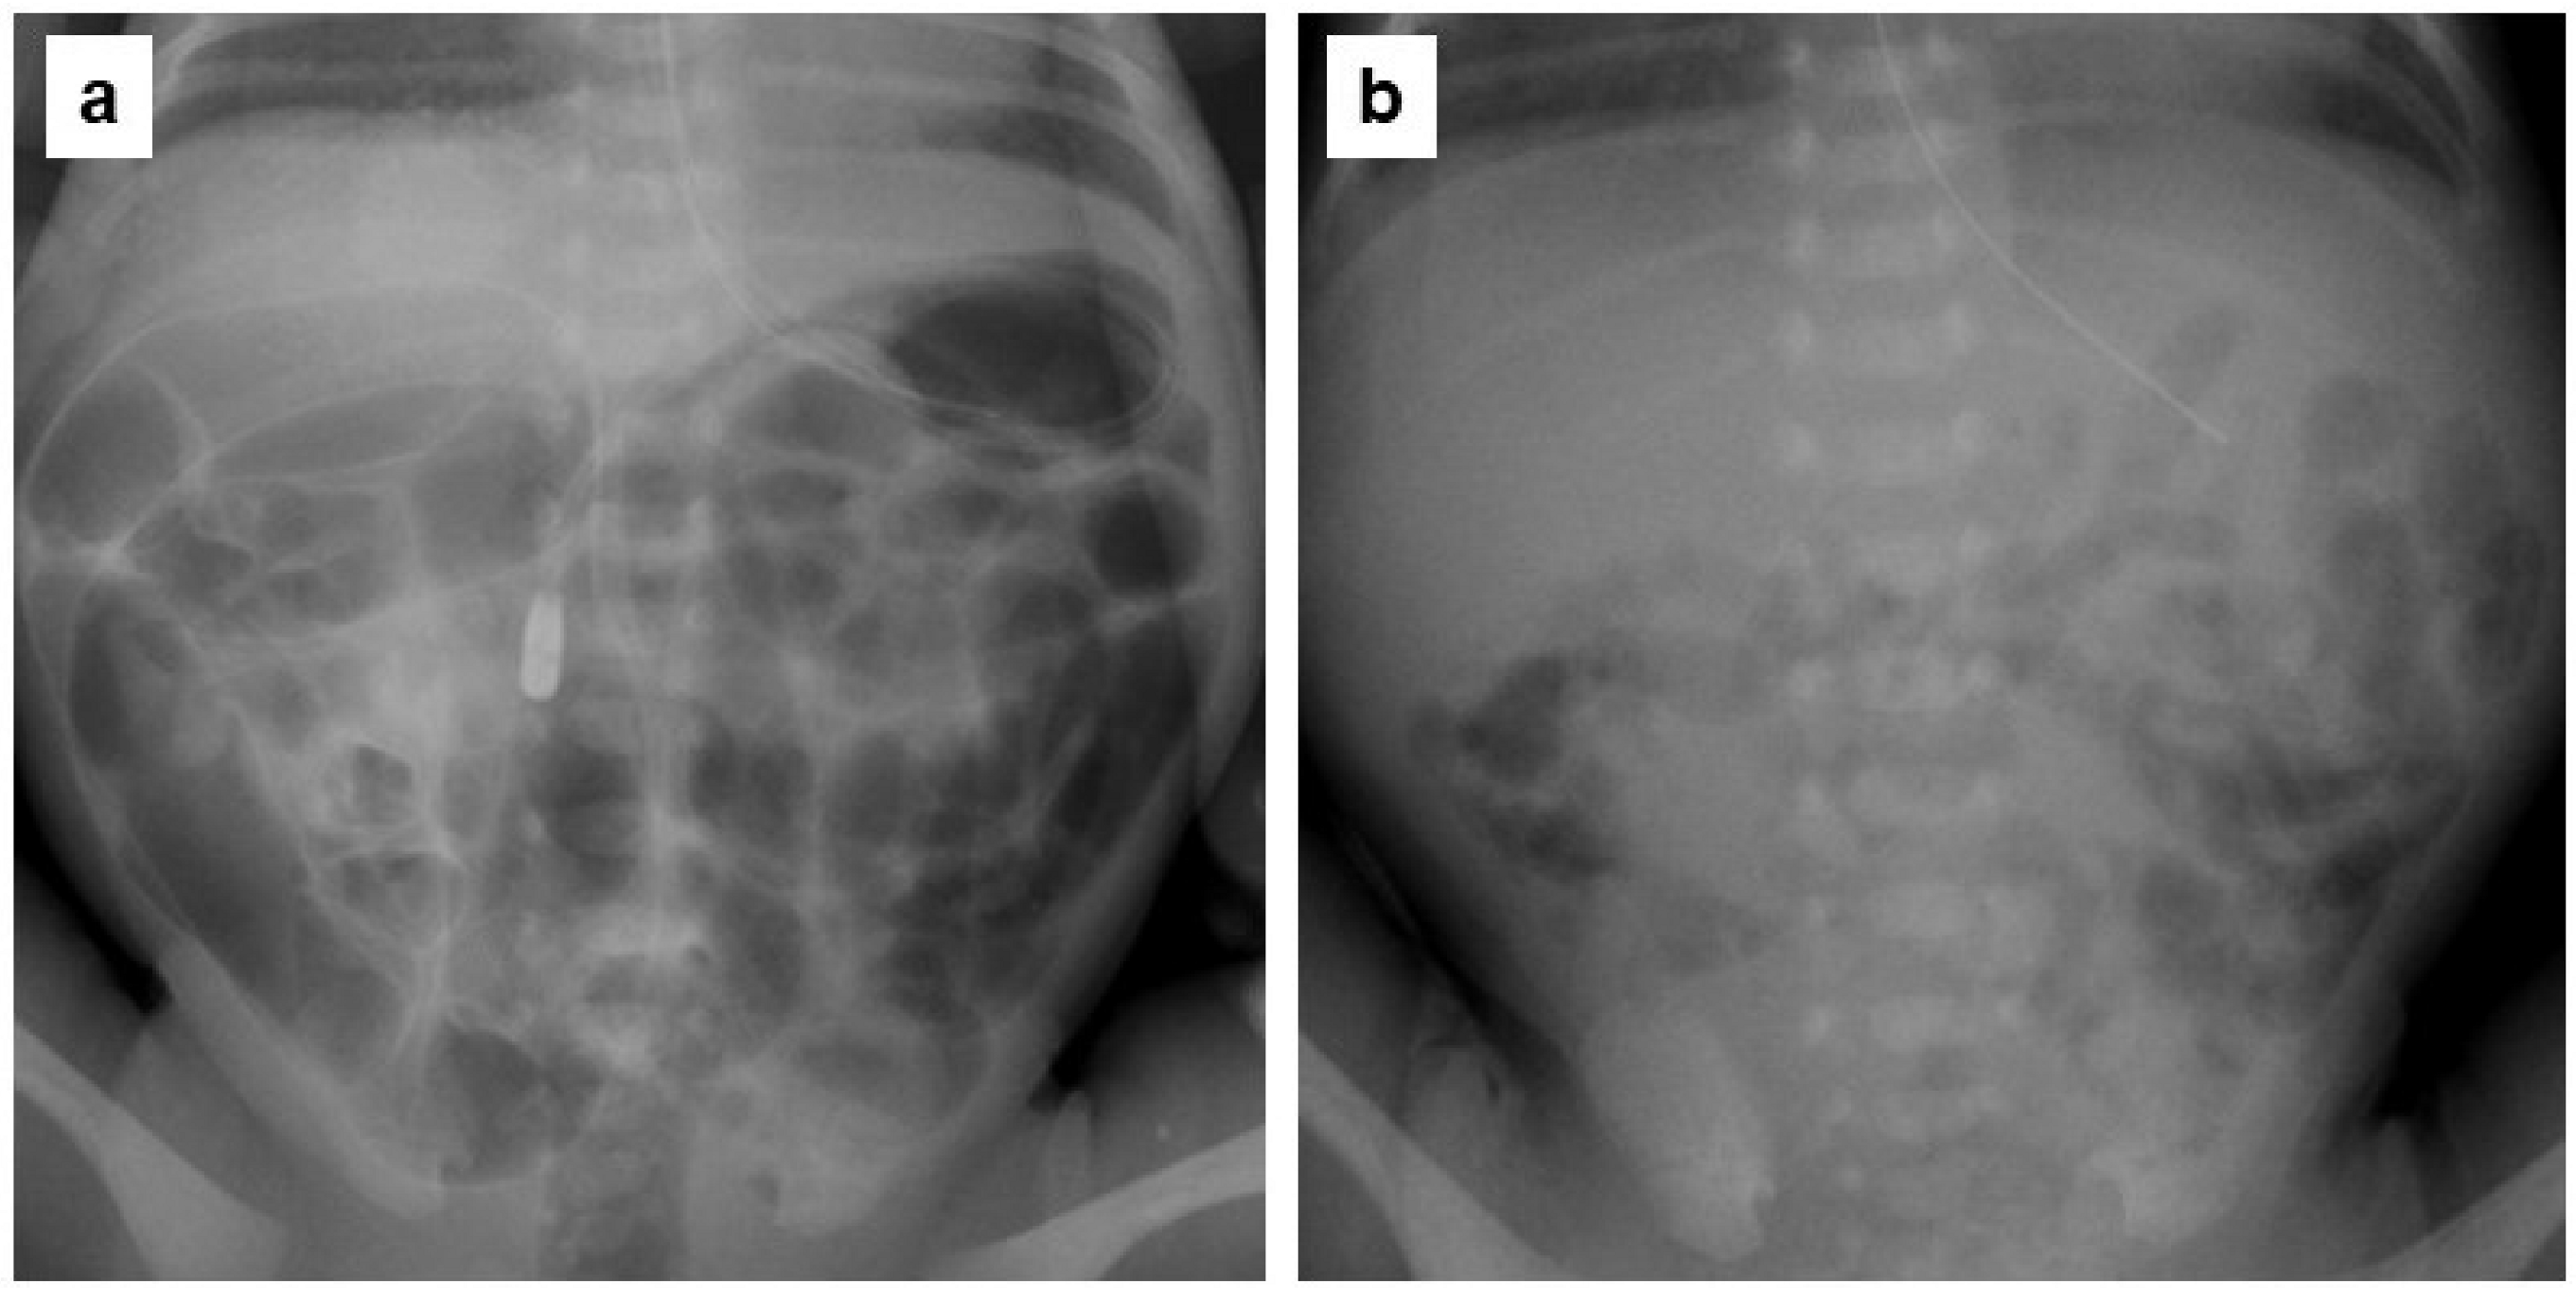

2.5. Evaluation of Abdominal Gas Areas

- Koide, A.; Yamaguchi, T.; Odaka, T.; Koyama, H.; Tsuyuguchi, T.; Kitahara, H.; Ohto, M.; Saisho, H. Quantitative analysis of bowel gas using plain abdominal radiograph in patients with irritable bowel syndrome. Am. J. Gastroenterol. 2000, 95, 1735–1741. [Google Scholar] [CrossRef]

| Gas volume score (GVS) | 0.40 (0.31–0.49) | 0.30 (0.24–0.38) | 0.31 (0.23–0.35) | 0.008 |

| Reduction of GVS, n (%) | - | 22 (92) | 20 (83) | 0.39 |

| ≥20% reduction of GVS, n (%) | - | 11 (46) | 11 (46) | 1.0 |